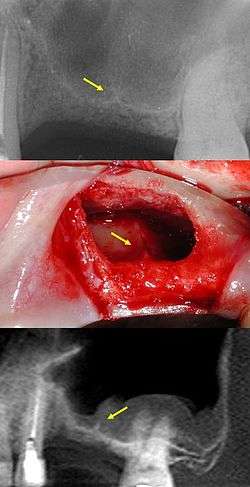

In anatomy, Underwood's septa (or maxillary sinus septa, singular septum)[1][2] are fin-shaped projections of bone that may exist in the maxillary sinus, first described in 1910 by Arthur S. Underwood, an anatomist at King's College in London.[3] The presence of septa at or near the floor of the sinus are of interest to the dental clinician when proposing or performing sinus floor elevation procedures because of an increased likelihood of surgical complications, such as tearing of the Schneiderian membrane.[4]

The prevalence of Underwood's septa in relation to the floor of the maxillary sinus has been reported at nearly 32%.[5]

Primary vs. secondary septa

Recent studies have classified two types of maxillary sinus septa: primary and secondary. Primary septa are those initially described by Underwood and that form as a result of the floor of the sinus sinking along with the roots of erupting teeth; these primary septa are thus generally found in the sinus corresponding to the space between teeth, as explained by Underwood. Conversely, secondary septa form as a result of irregular pneumatization of the sinus following loss of maxillary posterior teeth.[6] Sinus pneumatization is a poorly understood phenomenon that results in an increased volume of the maxillary sinus, generally following maxillary posterior tooth loss, at the expense of the bone which used to house the roots of the maxillary posterior teeth.